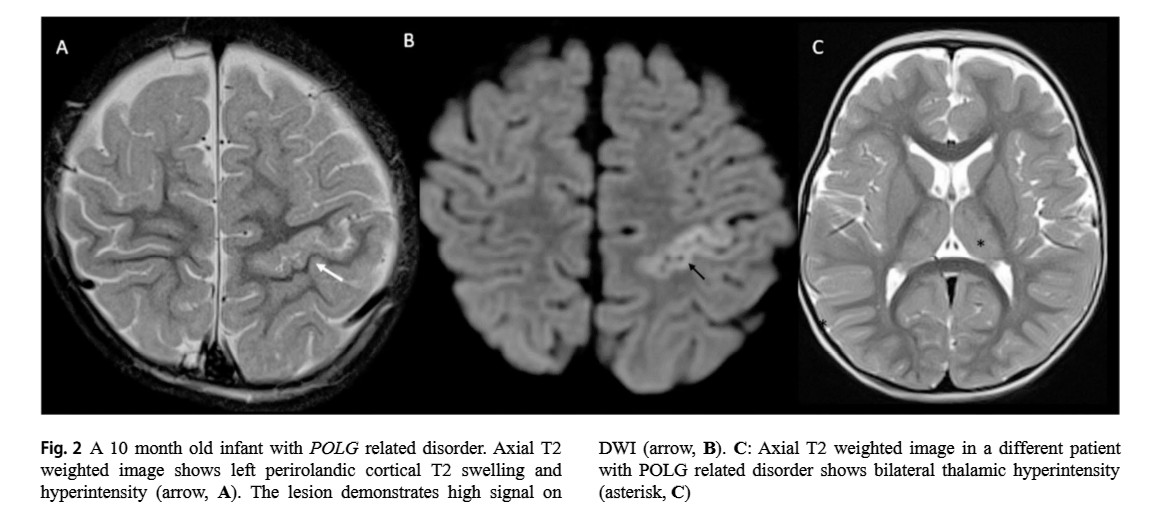

Our paper on imaging phenotypes of mitochondrial disorders is now out! Grateful to my brilliant co-authors @GaurPritika @cesaralvesneuro @SSudhakar2019 @drmankad @drharunyildiz and Dr. Rahman. Full text link here: https://t.co/nmHW9JMGBO

Fresh! 👍♥️🙋‍♂️ Imaging patterns of paediatric CNS mitochondrial disorders https://t.co/M3ohYWjbLW #radiologicalillustration ✍️ pixel by pixel handmade!